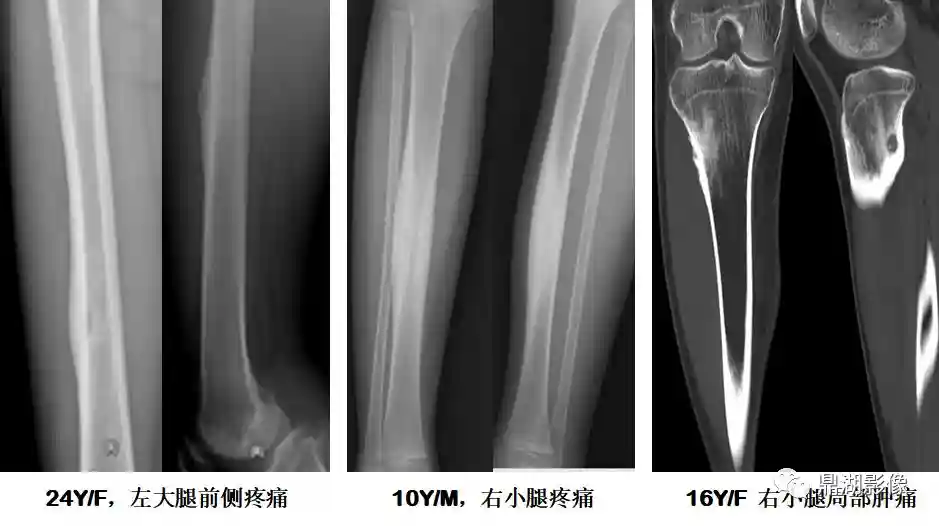

非骨化性纤维瘤

由纤维组织构成,无成骨,并为骨壳所包绕,周围骨组织反应性增生

5-20岁常见,好发于四肢长骨,以胫骨、股骨最为多见

多在外伤后发现,少数表现为局部疼痛

干骺端偏骨干侧,轻度膨胀多房病变;病灶长轴与骨干一致;无骨化